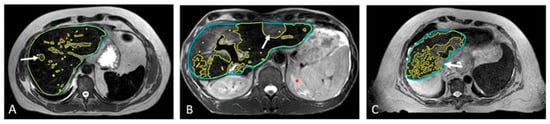

Compared to the pre-SPION image sets, SPIONs improved tumor visibility in the post-SPION images. The tumor boundary is clearly shown in the post-SPION images across all primary and metastatic liver tumors (Figure 3d–f), with negatively enhanced liver parenchyma.

As illustrated in Figure 4, SPIONs ensured consistent tumor visibility throughout the entire treatment course of the MR-guided liver SBRT, which had a median duration of 15 days (ranging from 5 to 28 days).

Figure 3. Pre- and post-SPION MR images of HCC (arrows) in the first and second row, respectively.

Figure 4. Example of four daily MR image sets used for online treatment plan adaptation targeting solitary colon cancer metastasis (white arrow) with SBRT (50 Gy in 4 fractions). Days 19, 21, 24, and 28 indicate the time elapsed since Ferumoxytol® injection, corresponding to sequential SBRT fractionation (fx).

Compared to pre-SPION image sets, SPION significantly enhanced tumor visibility in post-SPION images of HCC and hepatic metastases (Figure 3 and Figure 4). Tumor boundaries were clearly delineated against the negatively enhanced functional liver parenchyma in the post-SPION images (Figure 3, Figure 4 and Figure 6).

The prolonged retention of SPION contrast within the hepatic parenchyma enabled per-fraction treatment plan adaptation using SPION-enhanced MR imaging of the tumor and functional hepatic parenchyma throughout the entire treatment course, which had a median duration of 15 days (ranging from 5 to 28 days), without the need for repeated contrast administration.